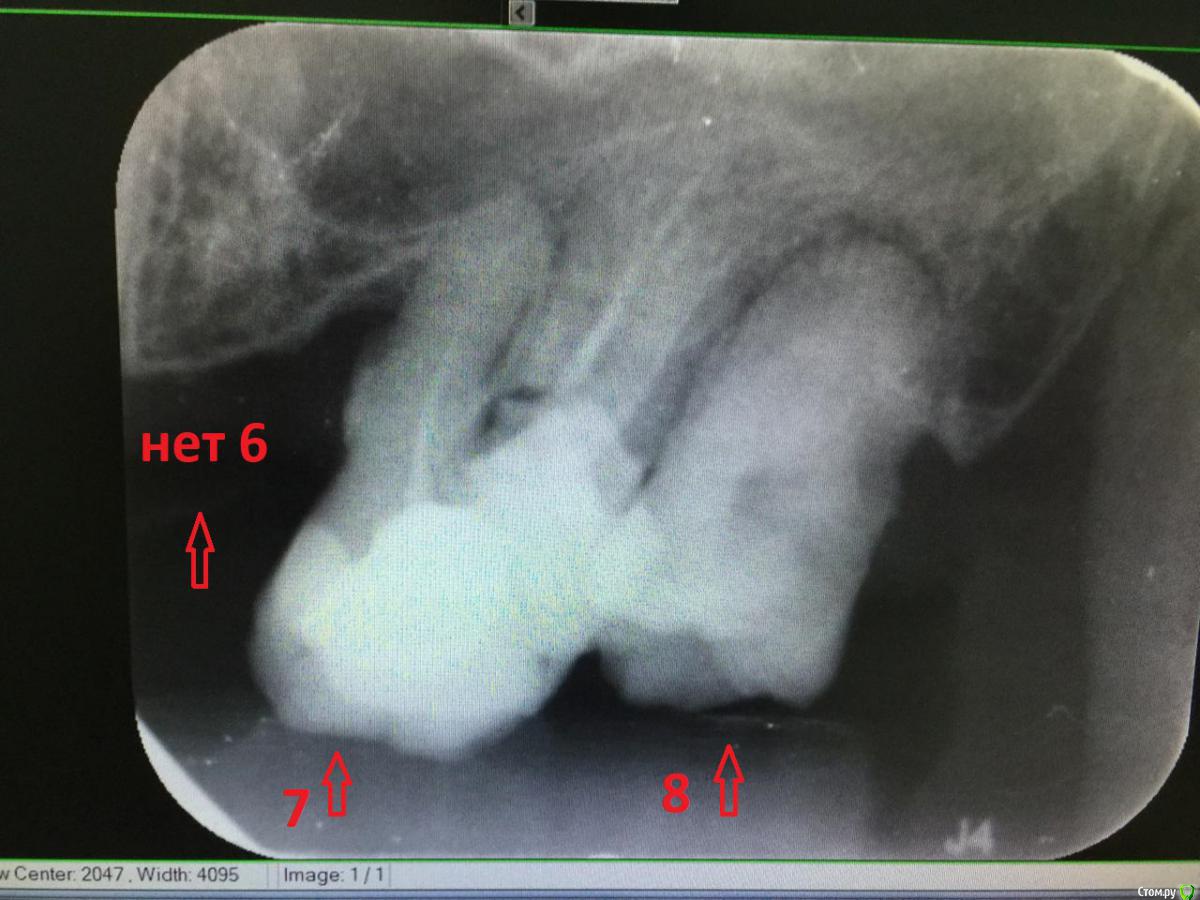

dentikl Опубликовано 26 сентября, 2019 Поделиться Опубликовано 26 сентября, 2019 Я один вижу только одного а не 5? Если не трудно, в 2х -3х словах, объясните что с ними? Объяснение на тайском недоступно, по английски, тайскому врачу было трудно объяснить. Я отстану сразу. Обещаю. 2 сообщения (мои и коллеги) и 4 "согласия" коллег (Они в цифрочках) которые просто не хотят повторятся и согласны с решением.Если в двух словах-оба зуба без кости (стоят в мягких тканях)(( по снимку ,который Вы предоставили)) Ссылка на комментарий

St. Опубликовано 27 сентября, 2019 Поделиться Опубликовано 27 сентября, 2019 Основная проблема в том что зубы разрушены достаточно сильно и кость вокруг них рассосалась. То есть в челюсти они держатся только кончиком корня и десной. Таблетки сейчас снимут дискомфорт, но вопрос удаления все равно актуален 2 Ссылка на комментарий